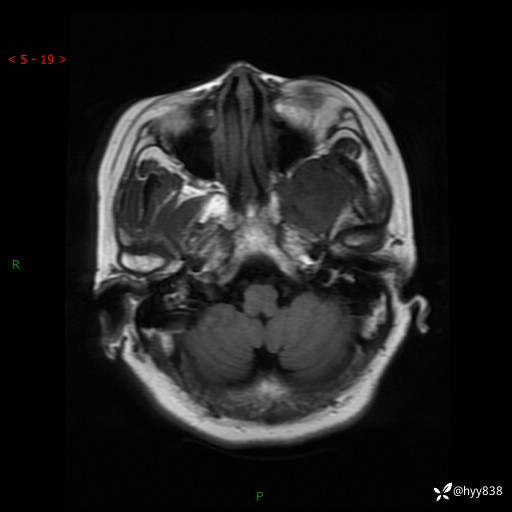

现病史:患者于1个月前无明显诱因出现左眼视力下降,无头痛,无恶心、呕吐,无肢体活动障碍,无意识障碍等伴随症状,后就诊于监利市人民医院行眼眶MRI检查提示“左侧中颅窝底占位性病变”,今日为求进一步诊治前来我院,门诊以“颅内占位性病变”收入院。 发病以来,患者精神、饮食及睡眠良好,大、小便正常。

颅脑MRI平扫+增强